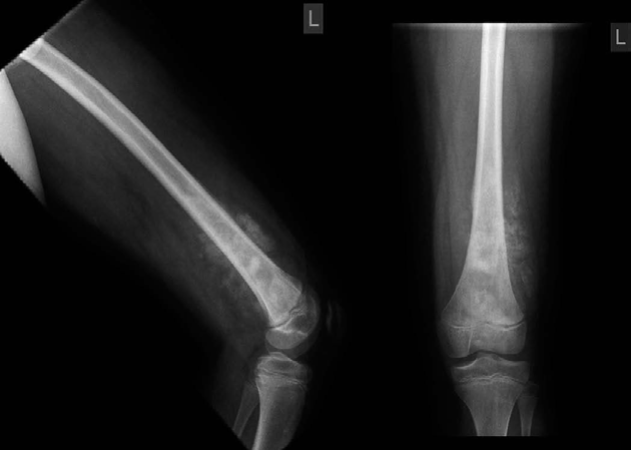

Orthopaedic oncology Structured oral examination question 6: Osteosarcoma EXAMINER : This young lad presented…